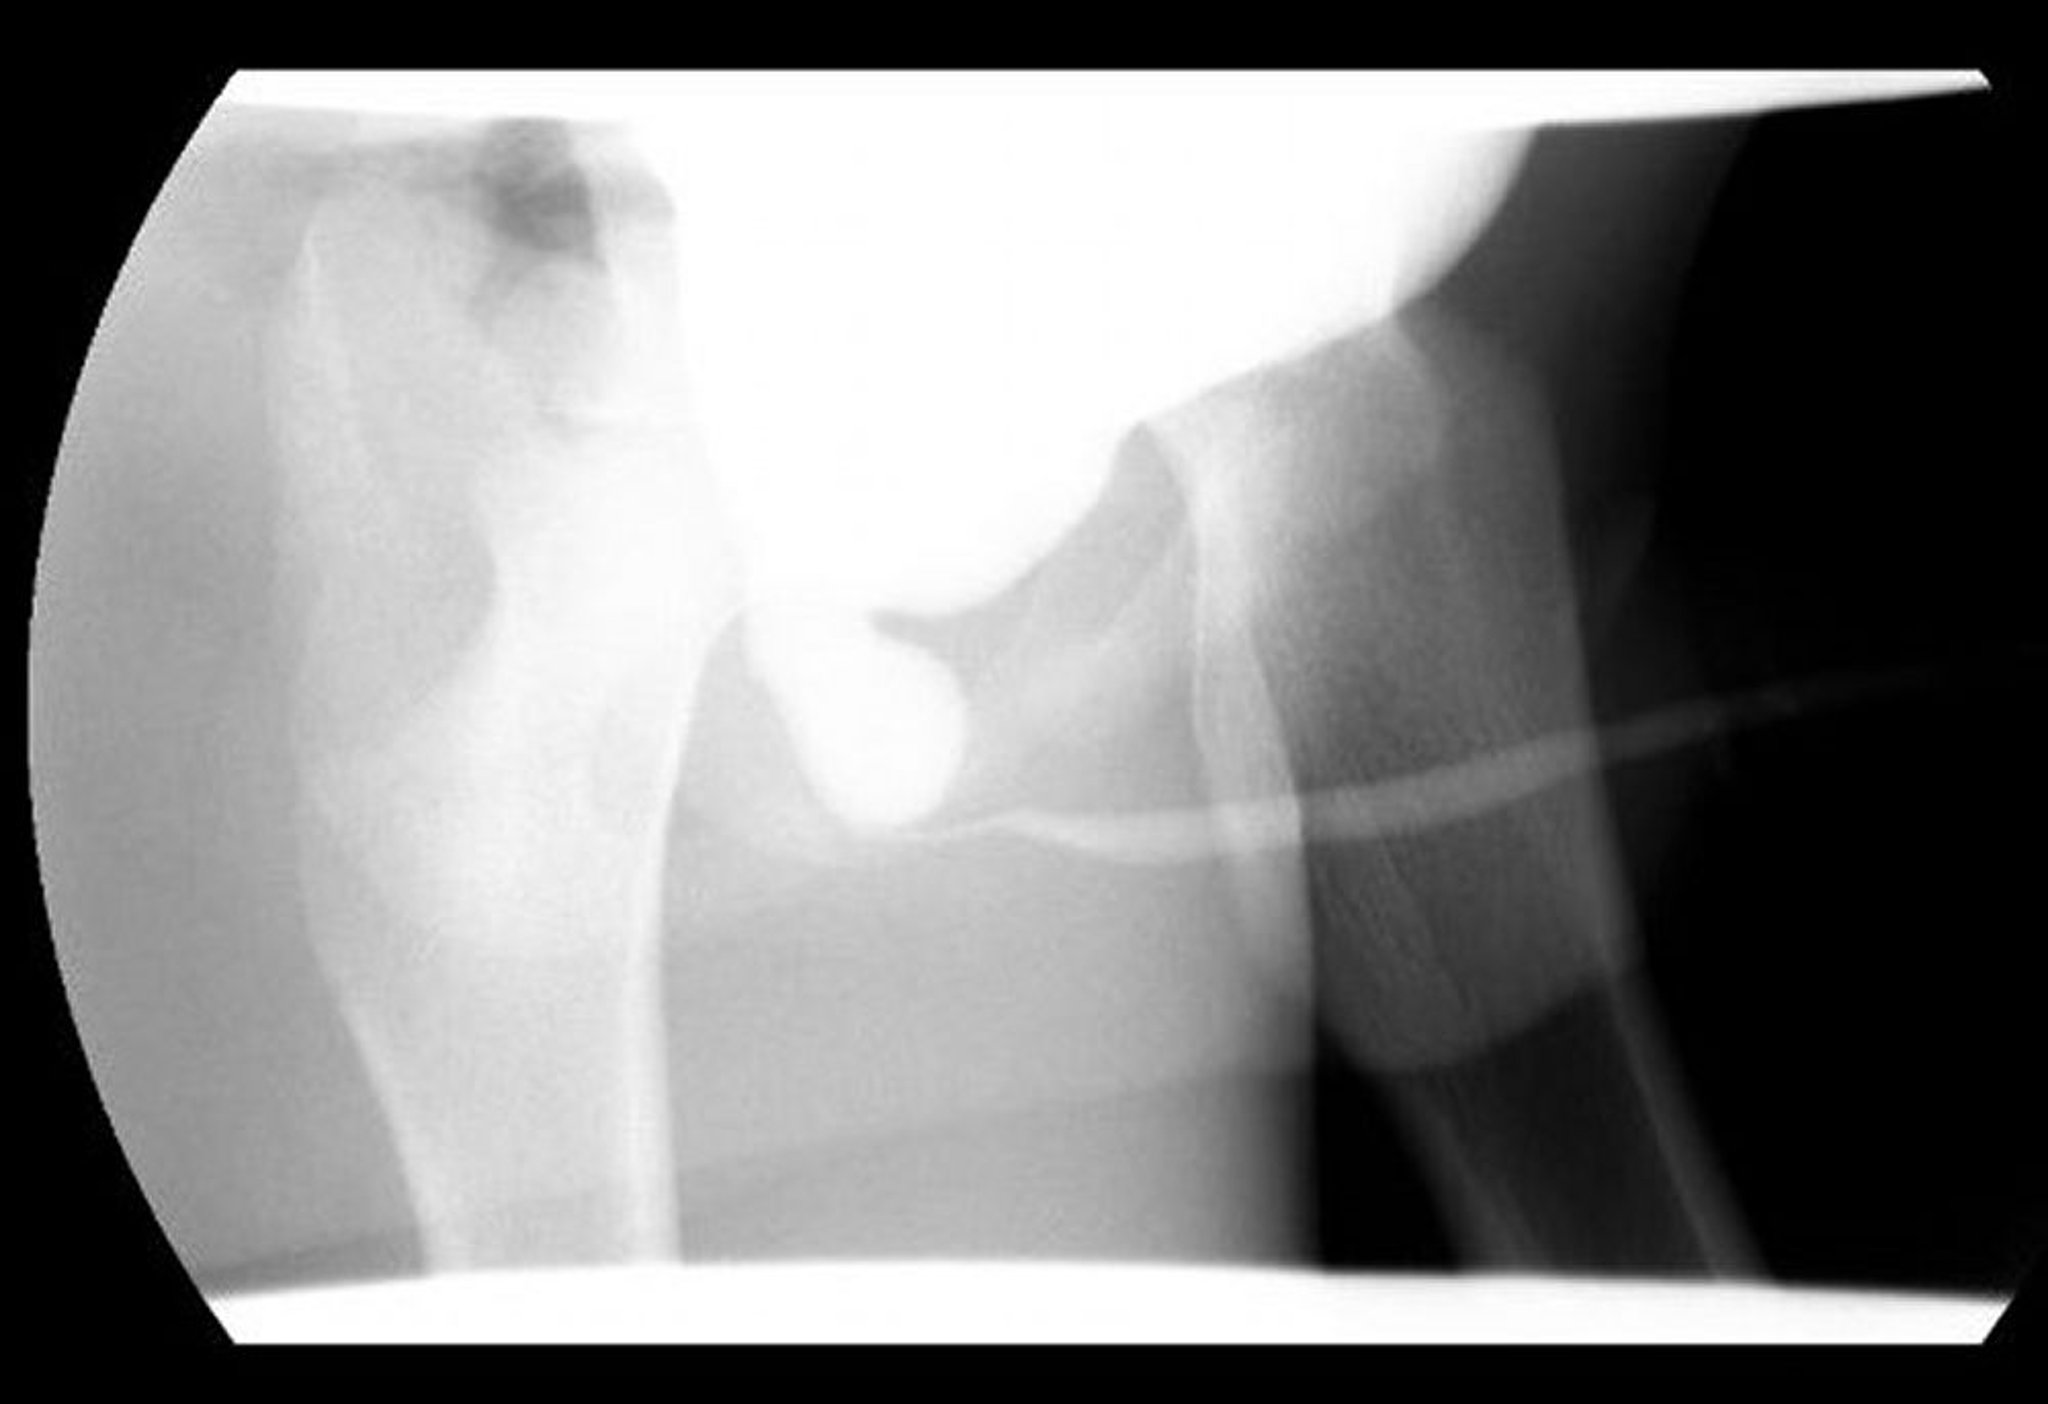

Essa imagem da uretrocistografia miccional (UCM) mostra uretra posterior dilatada com obstrução distal decorrente de valvas uretrais posteriores.

Imagem cedida por cortesia dos Drs. Ronald Rabinowitz e Jimena Cubillos.